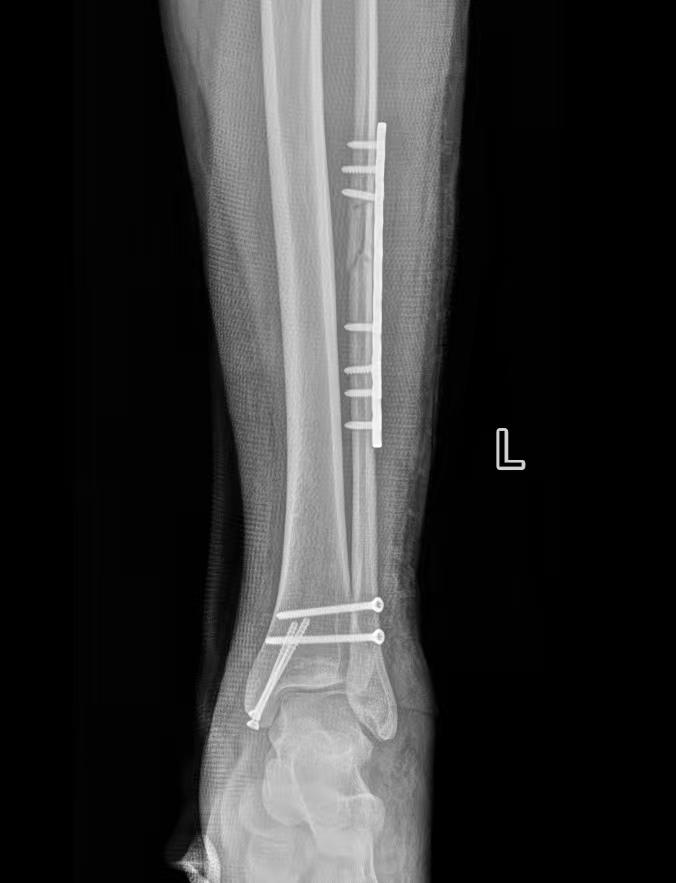

患者因意外受伤后踝关节疼痛、肿胀、无法行走,急诊就诊于我院。

经检查确诊为旋前外旋 Ⅳ 度踝关节骨折,包含腓骨中段骨折、内踝骨折、后踝骨折及下胫腓联合分离,属于临床中结构复杂、稳定性破坏较严重的踝关节损伤。

术中严格遵循骨科诊疗规范,完成骨折复位与固定,手术过程顺利。